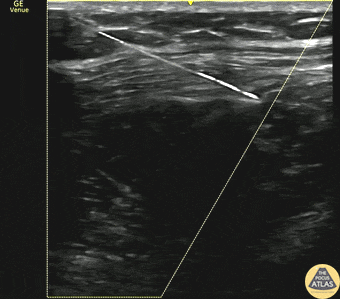

20s M presented with acute onset atraumatic chest pain, and was found to have a large spontaneous pneumothorax on chest radiography. To augment pain control for chest tube placement, a serratus anterior plane block was placed using 20 mL of 0.5% bupivacaine and 20 mL of 1% lidocaine. The block is shown here, where the needle is seen in-plane instilling anesthetic in the plane between latissimus dorsi superficially and serratus anterior deeply. The anechoic pocket of anesthetic is seen to spread between the two muscles and dissipates quickly after injection is paused, indicating successful placement. This patient had adequate pain control and was able to have a pigtail chest tube placed and was admitted to the hospital. Dr. Matthew Riscinti, Fellowship Director Denver Health Ultrasound Fellowship